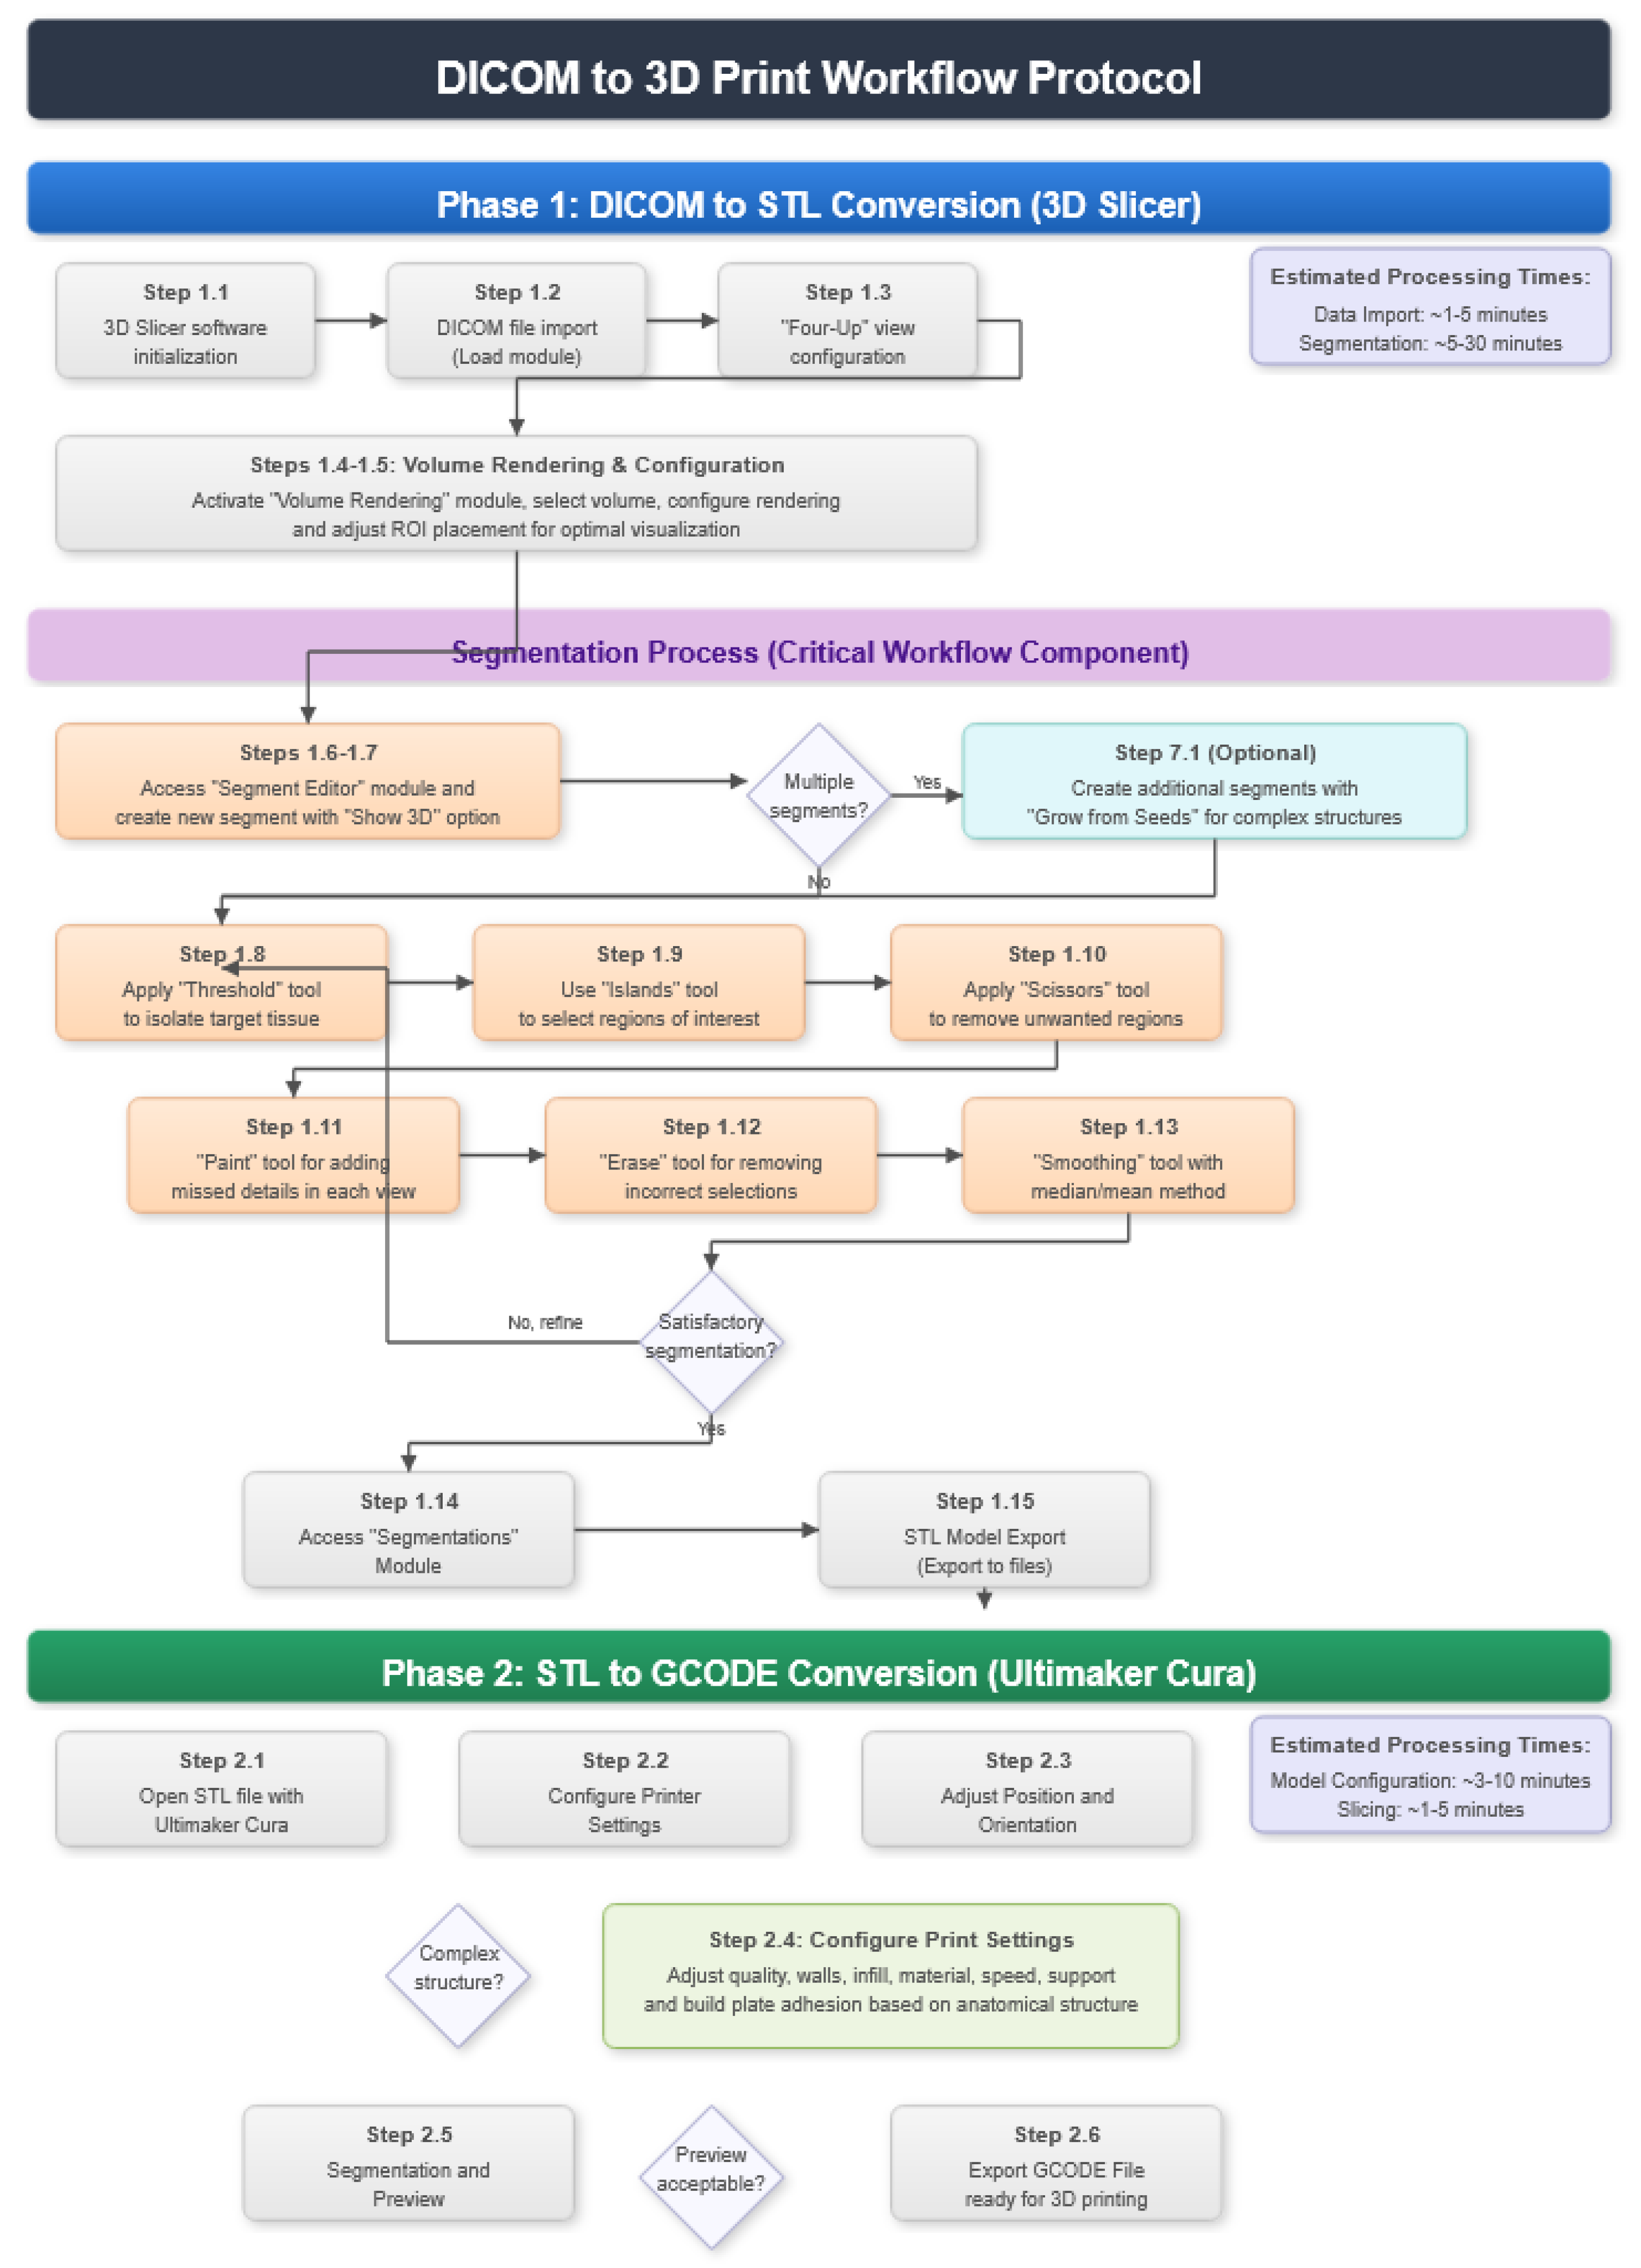

2. Protocol Description

2.1. DICOM-to-STL File Conversion

- At the DICOM module, select “Load” in order to import the corresponding DICOM file for the medical image of interest.

- Go to the “Layout Selection” in the tool bar, and select “Four-Up” view. This configuration allows for the visualisation of DICOM images in three different views, along the 3D view.

- Select the “Volume Rendering” module in the toolbar.

- Select the volume of interest in the drop-down menu, and activate the rendering function.

- Configure the rendering process by accessing the “Display” drop-down. Choose the most appropriate “preset” option in terms of the image and anatomical model tissue.

- Use the Shift function to adjust the rendered visible tissues, and enable the “Crop” option in order to cut the “region of interest”.

- Make the Region of Interest (ROI) display visible in order to visualise it, and adjust the ROI volume rendering square in the region of interest for the 3D view.

- Go to the “Segment Editor” module in the toolbar.

- Select “Add new empty segment”, and assign a descriptive name to the segment.

- Press “Show 3D” to visualise the segment in the corresponding 3D View.

- Creation of new segments: Start the creation of additional segments for the corresponding structures.

- “Grow from Seeds” tool: Select the “Grow from Seeds” tool for a more detailed segmentation.

- Seed placement: Identify and select reference points or seeds inside the regions to be segmented.

- Initiate the segmentation process: Activate the “Grow from Seeds” function, and allow the tool to expand the segmentation from the seeds to the adjacent regions.

- Select “Threshold” tool.

- Adjust the threshold of the Threshold range until it includes the entire region of interest, and apply the settings.

- Use the “Islands” tool.

- Select the “Keep selected islands” option, and mark the areas of interest in one of the views.

- Select the “Scissors” tool.

- Configure the options “Erase inside”, “Free-form’,’ and “Unlimited”.

- In the views, select and delete unwanted parts until the desired anatomical structure is obtained.

- Use the “Paint” tool.

- Paint those parts which have not been selected yet and which form part of the model for each one of the “cuts” of the three views.

- Use the “Erase” tool.

- Paint the selected parts, which do not form part of the model for each cut in the three views.

- Select the “Smoothing” tool.

- Choose the “median” or “mean” method, and configure the kernel size as needed.

- Go to the “Segmentations” Module in the toolbar.

- Go to “Export/import models and label maps”.

- In the menu, select “model” as the output option.

- In “Export to files”, choose the destination folder.

- Select the STL file format, and, finally, click on “Export”.

2.2. STL-to-GCODE File Conversion

- Launch the Ultimaker Cura program on your computer.

- Open the STL file you want to print from the “Open File” option in the menu.

- Access the printer settings within Ultimaker Cura.

- Be sure to select the appropriate printer model and material settings for your 3D printer.

- If necessary, make adjustments to the position, scale, or rotation of the model on the build platform within Ultimaker Cura. This allows you to optimise the layout of the model on the printing platform.

- Adjust the layer height and line width to refine the print quality, considering the balance between print resolution and time efficiency.

- The print quality can be improved by increasing the number of walls, which strengthens the structure and improves the surface final result. Adjust the wall line count and interior-to-exterior orientation to optimise for strength and aesthetics.

- Set the number of top and bottom layers, select a pattern for these surfaces, and enable flattening with a specific pattern if necessary. These adjustments influence the surface texture and structural integrity of the printed object.

- Determine the density and pattern of the infill, taking into account the trade-off between the weight of the object and its structural robustness. The fill-in sequence in relation to the wall print can also affect the final quality of the print.

- Set the print temperature, initial layer temperature, final temperature, and build plate temperature according to the filament material specifications to ensure optimal extrusion and adhesion. The flow rate may also need adjustment to achieve the desired extrusion quality. It is crucial to refer to the filament manufacturer’s guidelines for specific settings, as these can vary significantly between different materials and brands.

- Control the print speed to balance the print quality and time efficiency. Slower speeds typically result in higher-quality prints by allowing for more precise material deposition.

- Enable retraction to prevent dripping and threading by adjusting the distance and speed of retraction based on the printer capabilities and filament used.

- Adjust the fan speed to regulate cooling, which can significantly affect the print quality, especially on overhangs and bridges. It is important to note that the optimal cooling configuration will vary depending on the printing material used since each material has different thermal properties that affect its behavior against rapid cooling.

- Choose the appropriate support structure type and pattern to ensure the successful printing of complex geometries, adjusting the adhesion to the build plate as necessary.

- Select an adhesion type to improve the first coat’s adhesion to the build plate, reducing problems associated with poor first coat adhesion.

- In order to continue the STL file to GCODE conversion process, select the “Segmentation” option in Ultimaker Cura.

- The segmentation tool provides valuable information such as the estimated model weight and estimated printing time, among other crucial data.

- Once the segmentation is complete, go to the “Preview” option. Here, a sidebar will appear on the right side of the screen, giving you the ability to preview the materialisation process layer by layer, from the base to the top of the model.

- Once all the print settings are configured, select the “File” option in the Ultimaker Cura menu.

- Choose the “Export” option, and select “GCODE” as the output file type.

- Save the GCODE file to the desired location for later use in your 3D printer.